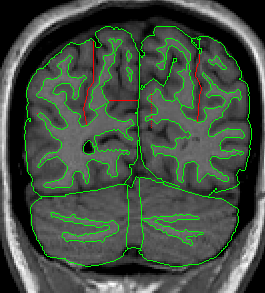

Once you have drawn your sulci lines, the insula should be clearly outlined (by little dots) in the coronal view (Fig 3). This is particularly useful in the more anterior slices.

Figure 3